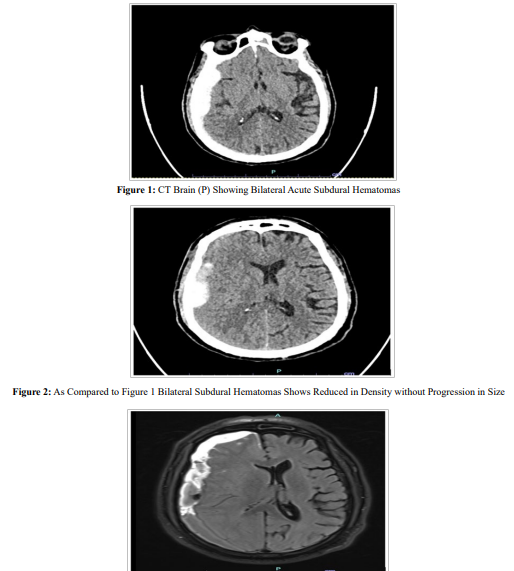

A 70-year male, background of hypertension, IHD, DM on blood thinner medications presented in Department of Neurosurgery with severe headache for 2 days. Routine blood investigations were normal. Neurological examination revealed mild right sided pronator drift. CT Brain showed bilateral acute subdural hematomas (R>L). Patient was started on iv antiepileptics, analgesics and anti- oedema drugs. Blood thinner medication was stopped and opinion from cardiologist was taken for the same. 2D echo done showed 55% EF. After 4 days of conservative management repeat CT Brain was done which showed decrease in SDH. However, on day 6 patient had sudden onset of left sided weakness and slurring of speech. Code purple was activated and MRI Brain was urgently done considering the possibility of stroke. However, MRI Brain done showed no signs of stroke and increase in SDH with 10 mm midline shift.

Figure 3: MRI Brain Showed Increase in Size of the Right Cerebral Convexity Subdural Hematoma with Interval Increase in the Midline Shift (Now 10 mm to the Left)